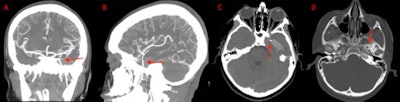

A 12-year-old boy in Texas experienced a seizure after an orthodontic wire from his braces migrated into his temporal lobe.

(A) and (B) Coronal and sagittal view of the CT angiogram shows the wire penetrating through the skull floor of a 12-year-old boy. (C) Axial view of CT demonstrates the wire in the temporal lobe and the associated intraparenchymal hemorrhage. (D) Axial bone window CT shows the wire entering through the foramen ovale. Image courtesy of Morgan et al. Licensed by CC BY 4.0.

After imaging confirmed the metallic foreign object, which had migrated via the foramen ovale into the temporal lobe, as well as an associated intraparenchymal hemorrhage, the wire was removed without complications. The boy sustained no measurable damage to any structures within or around the foramen ovale, including the carotid artery, which would have been devastating, according to the case report in Radiology Case Reports.